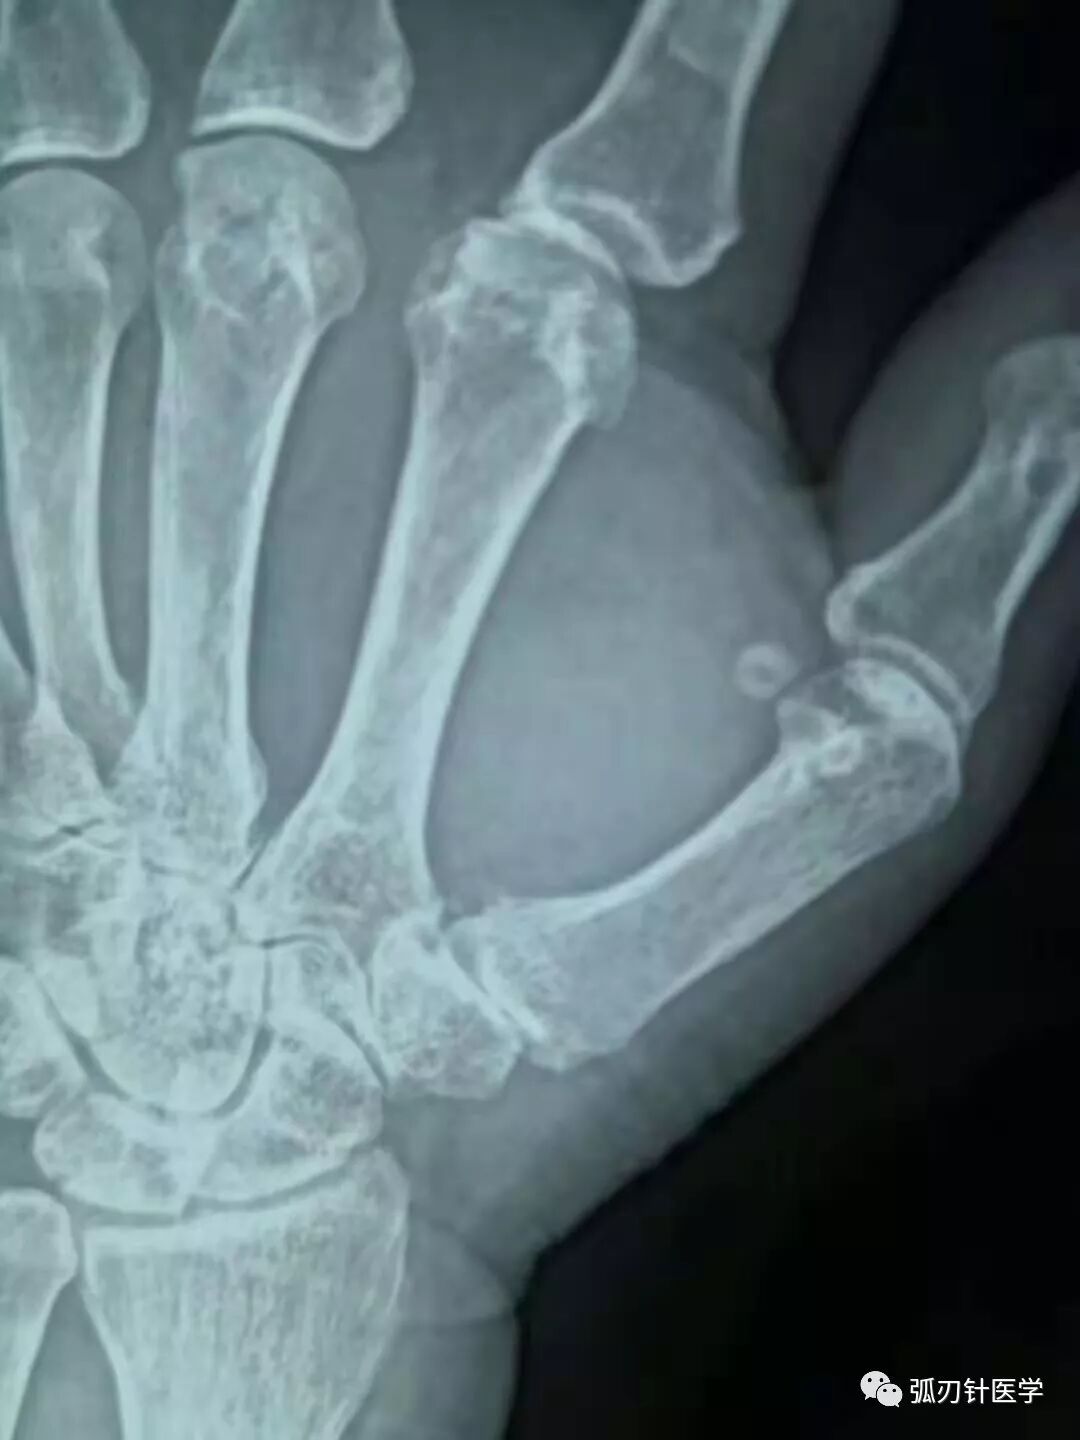

摘要: 右腕疼痛,考虑右手第一腕掌关节骨关节炎,不是腱鞘炎!猜你喜欢的文章一篇文章让你了解弧刃针技术全面学习弧刃针技术!12月12--15日第59期颈肩腰腿痛培训十合一精华班!弧刃针专题班(含解剖培训)12月12--14日郑州 ...

右腕疼痛,考虑右手第一腕掌关节骨关节炎,不是腱鞘炎!